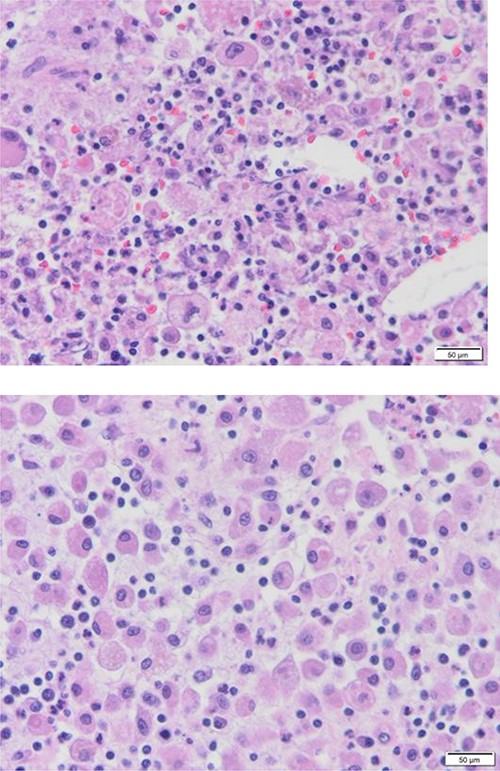

The patient evaluation and the data collection of gallbladder disease were prospectively performed at a single, private tertiary center, Dr Soliman Fakeeh Hospital (Jeddah, Saudi Arabia). The current study investigated the incidence of XGC in 1141 consecutive patients who underwent cholecystectomy in our institution between January 2019 and December 2021. We excluded pediatric age groups and patients who did cholecystectomy combined with other surgeries. The gallbladder disease was confirmed by ultrasonography (US), computed tomography (CT), magnetic resonance cholangiopancreatography (MRCP) and diagnostic laparoscopy. The measured outcome included surgical intervention, conversion to open and complication rate. Factors that might extend the length of hospital stay postoperatively were also evaluated. The Institutional Review Board approved the study protocol of Dr. Soliman Fakeeh Hospital with approval no. 228/IRB/2021. Of 1141 patients who underwent cholecystectomy, XGC was seen in 10 (0.87%). The average age was 47 (24–81 years). Six patients were male, and four were female, with a male-to-female ratio of 3:2. The patients’ nationalities varied, including Arab (8/10), Filipino, and Irish. Comorbidity was present in five patients. The average body mass index (BMI) was 30.8 (27.7–34.5). The duration of symptoms ranged between 1 and 12 weeks. The preoperative diagnoses were biliary colic (5/10), acute cholecystitis (3/10), biliary pancreatitis and obstructive jaundice. Endoscopic retrograde pancreaticography (ERCP) and stenting were done on two patients preoperatively. The average WBC was 8.3 x 10 3 (3.94–15.52), total bilirubin was 0.71 mg/dl (0.18–1.81) and international normalized ratio (INR) was 0.9 (1.2–0.98). The preoperative ultrasonography did not predict the presence of XGC or suggest the need for further imaging, except in one patient with soft-tissue mass inside the gallbladder. The average wall thickness was 5 mm (2–37), stone size was 7 mm [5–13], CBD diameter was 4.5 mm [2–7] and pericholecystic fluid was present only in 20% (2/10). One patient was described to have a mural diverticula and one pyocele. Four out of ten (40%) required more than 72 h of hospitalization. All patients underwent elective surgery with a laparoscopic approach. One patient required conversion to open due to a thickened 12 mm wall with perforation. The average operative time was 90 min (43–193), with no significant intraoperative event. The drain was inserted in 40% of the patients (4/10). One patient required excision of the liver bed; this section was frozen immediately and returned as negative for malignancy. No postoperative complications were listed over the median follow-up of 24 months (11–30). None of the patients had a postoperative collection, bleeding, surgical site infection, biliary leak or readmission. Tables 1 and 2 summarized the patients data. One patient was diagnosed preoperatively on images as suspicious of XGC versus malignancy. The characteristics shared histological features, including ulcerated mucosa with transmural acute and chronic inflammatory cell infiltrate, a sheet of foamy histocyte and multinucleated foreign body giant cell granuloma (Fig. 1).

Diffuse proliferation of histiocytes with foreign body giant cell granuloma, Hematoxylin and Eosin H&E, 40x high power filed.